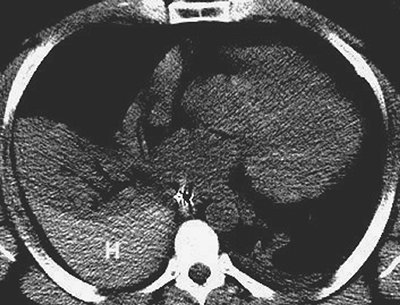

FIGURE 9-43. Elevated diaphragm secondary to hepatic hemangioma. A: CT scout image shows elevation of the right hemidiaphragm. B: Axial CT shows a large hepatic mass.